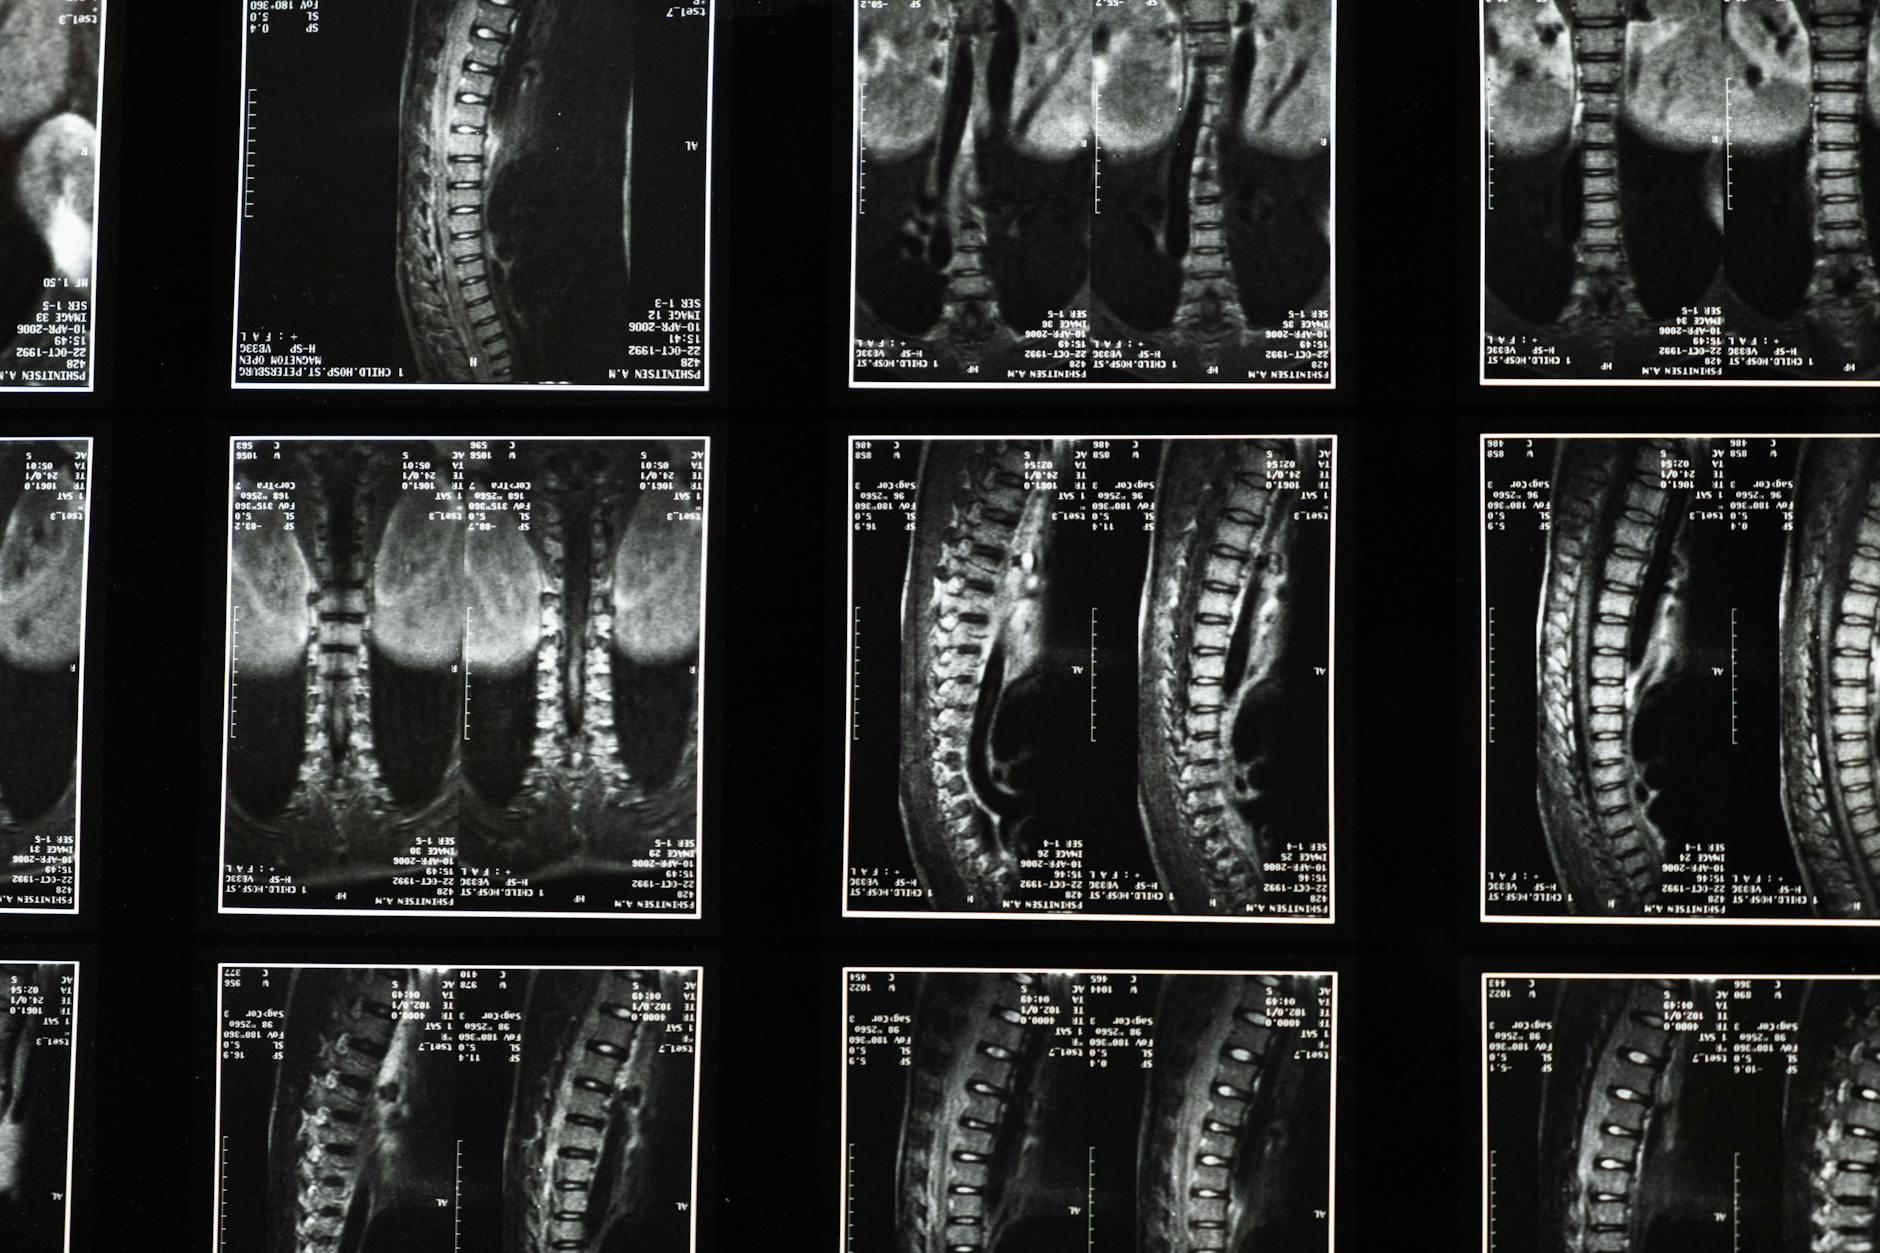

- [Thoát vị đĩa đệm]: Nhân nhầy của đĩa đệm bị lồi ra ngoài và chèn ép lên rễ thần kinh tọa, gây đau.

- Hẹp ống sống: Tình trạng ống sống bị thu hẹp, chèn ép lên dây thần kinh.

- Thoái hóa cột sống: Bao gồm các vấn đề như trượt đốt sống.